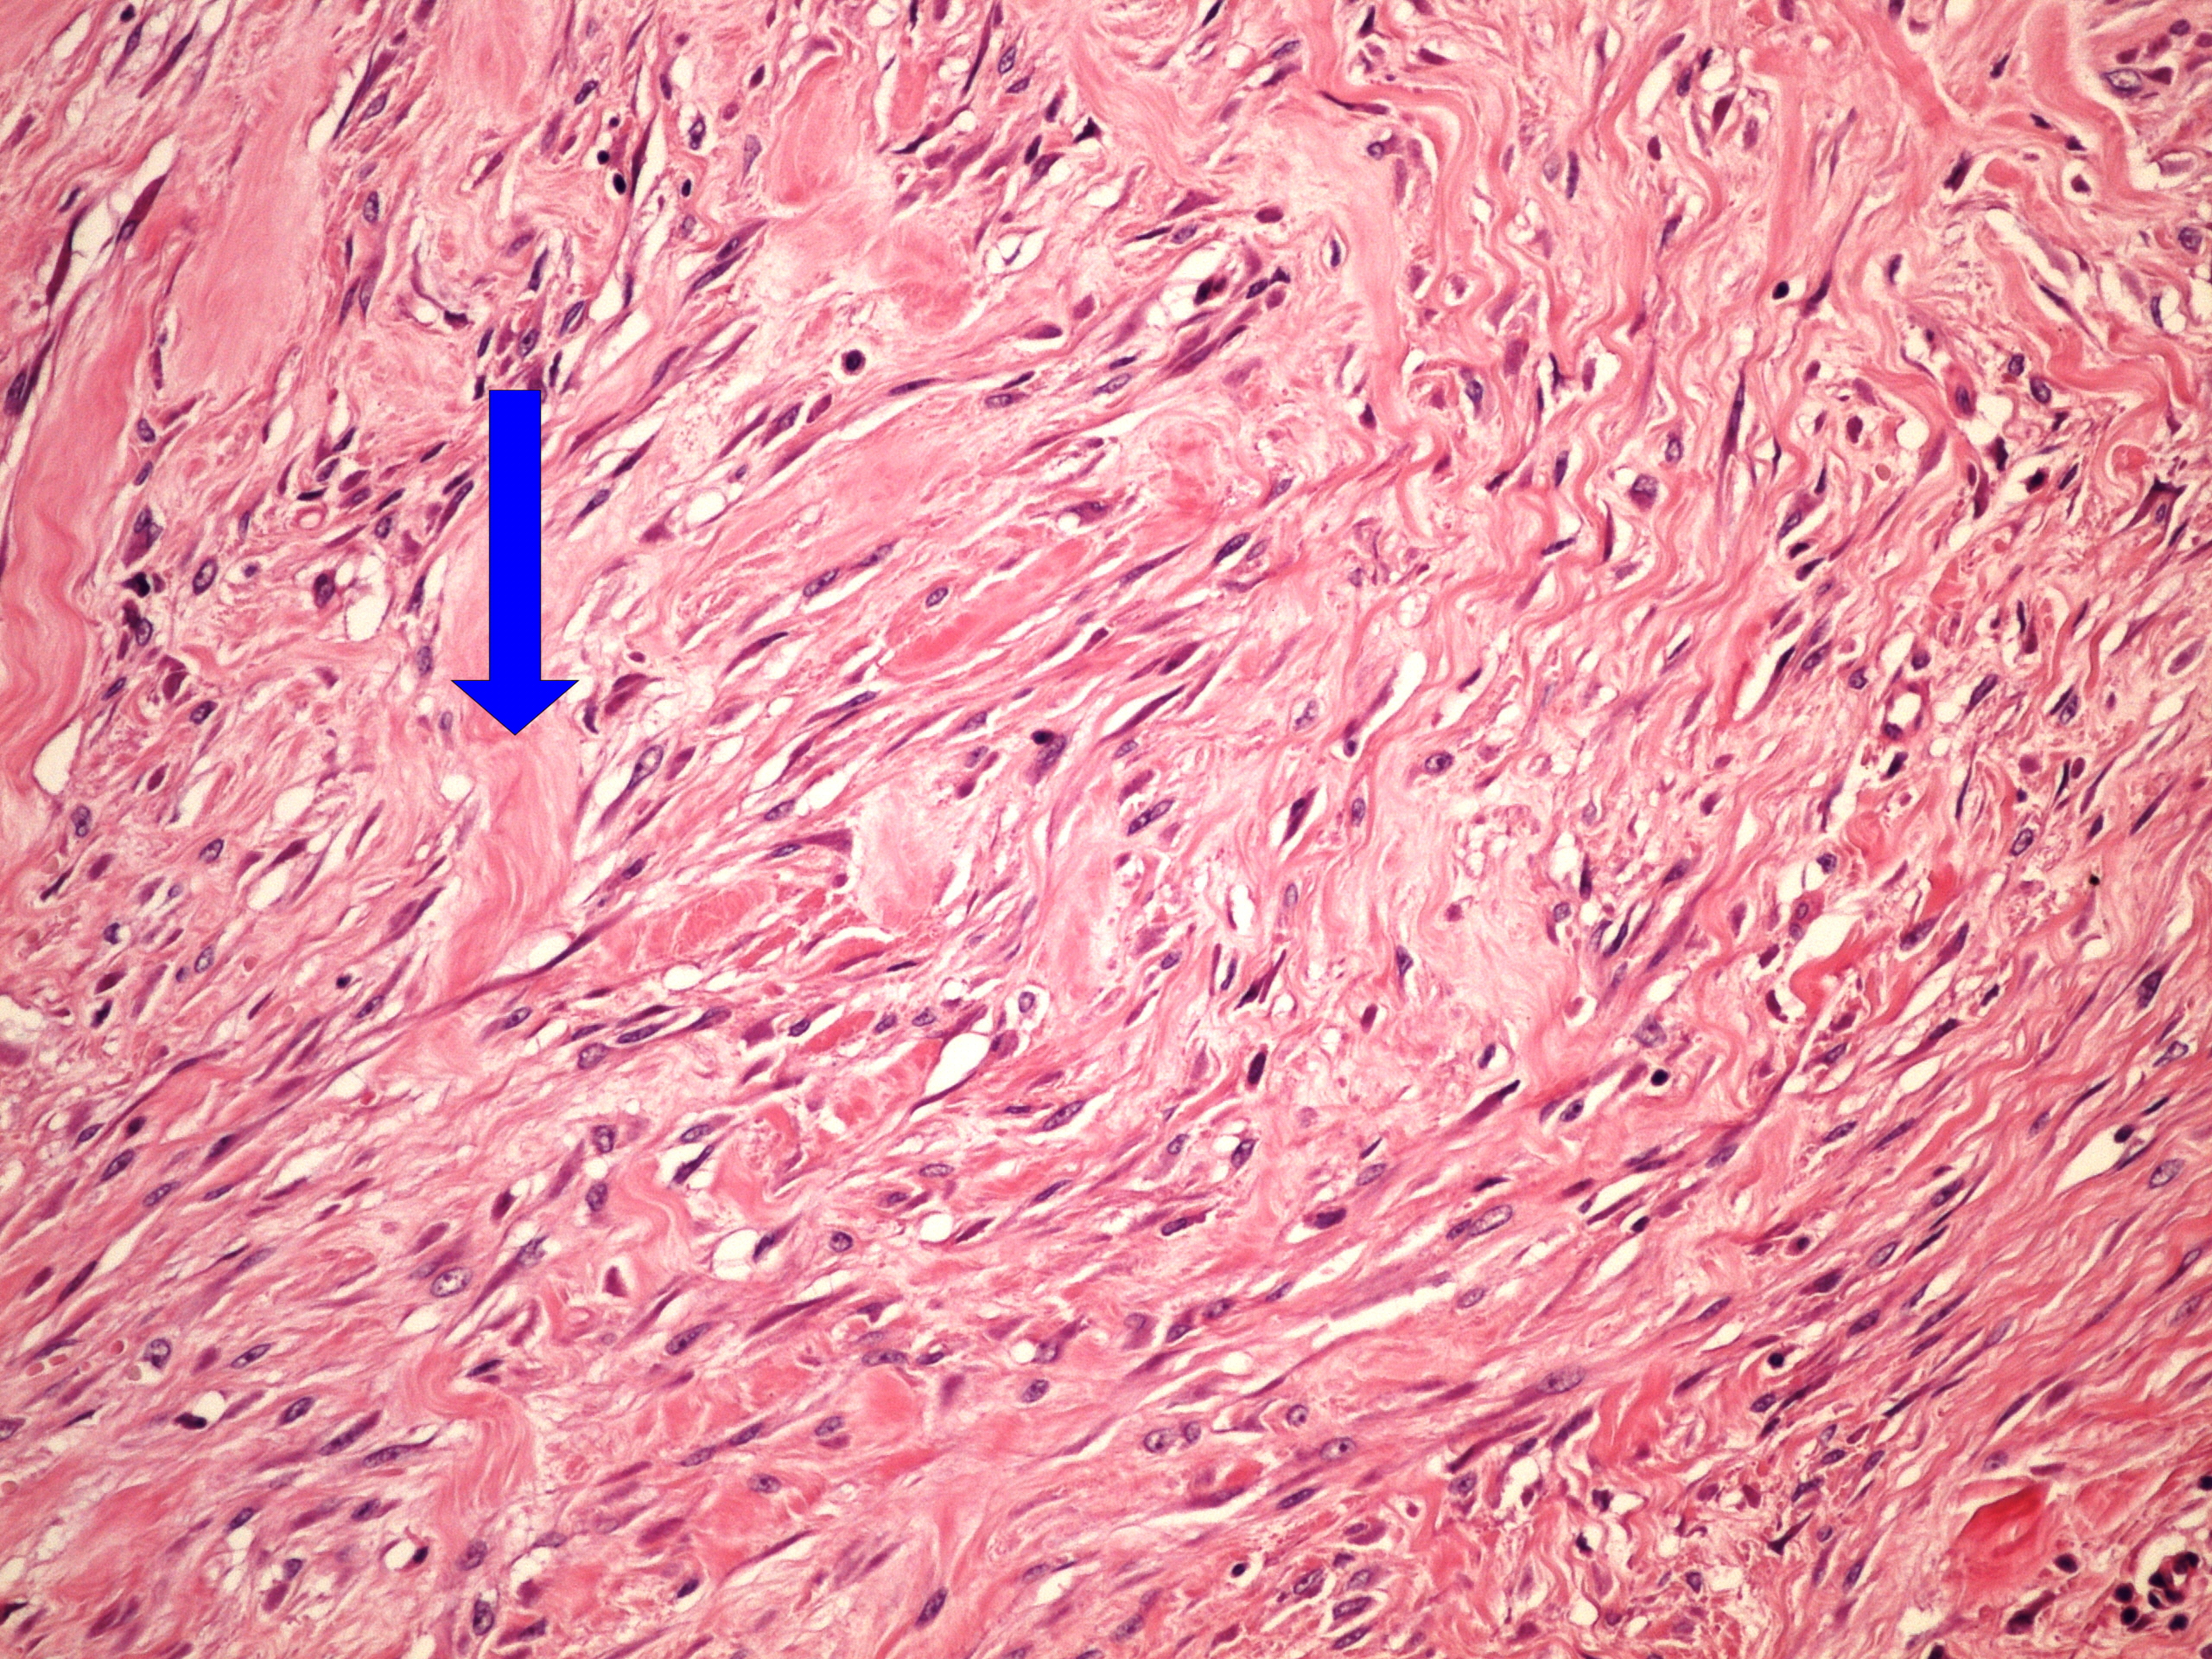

Preparát č.9 a č.10 - keloid

Struktury

- hrubé snopce kolagenního vaziva